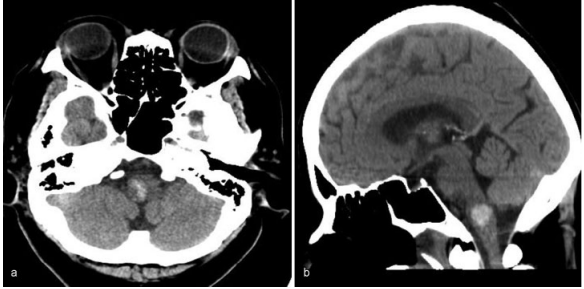

一位70岁的老人因为突然出现恶心和呕吐而被咨询到德国INI。右舌下神经麻痹导致右舌偏斜。她的血压是201/100毫米汞柱。电脑断层扫描(CT)显示右侧延髓出血

图:右侧延髓出血的电脑断层影像,(a)轴向(b)矢状面。